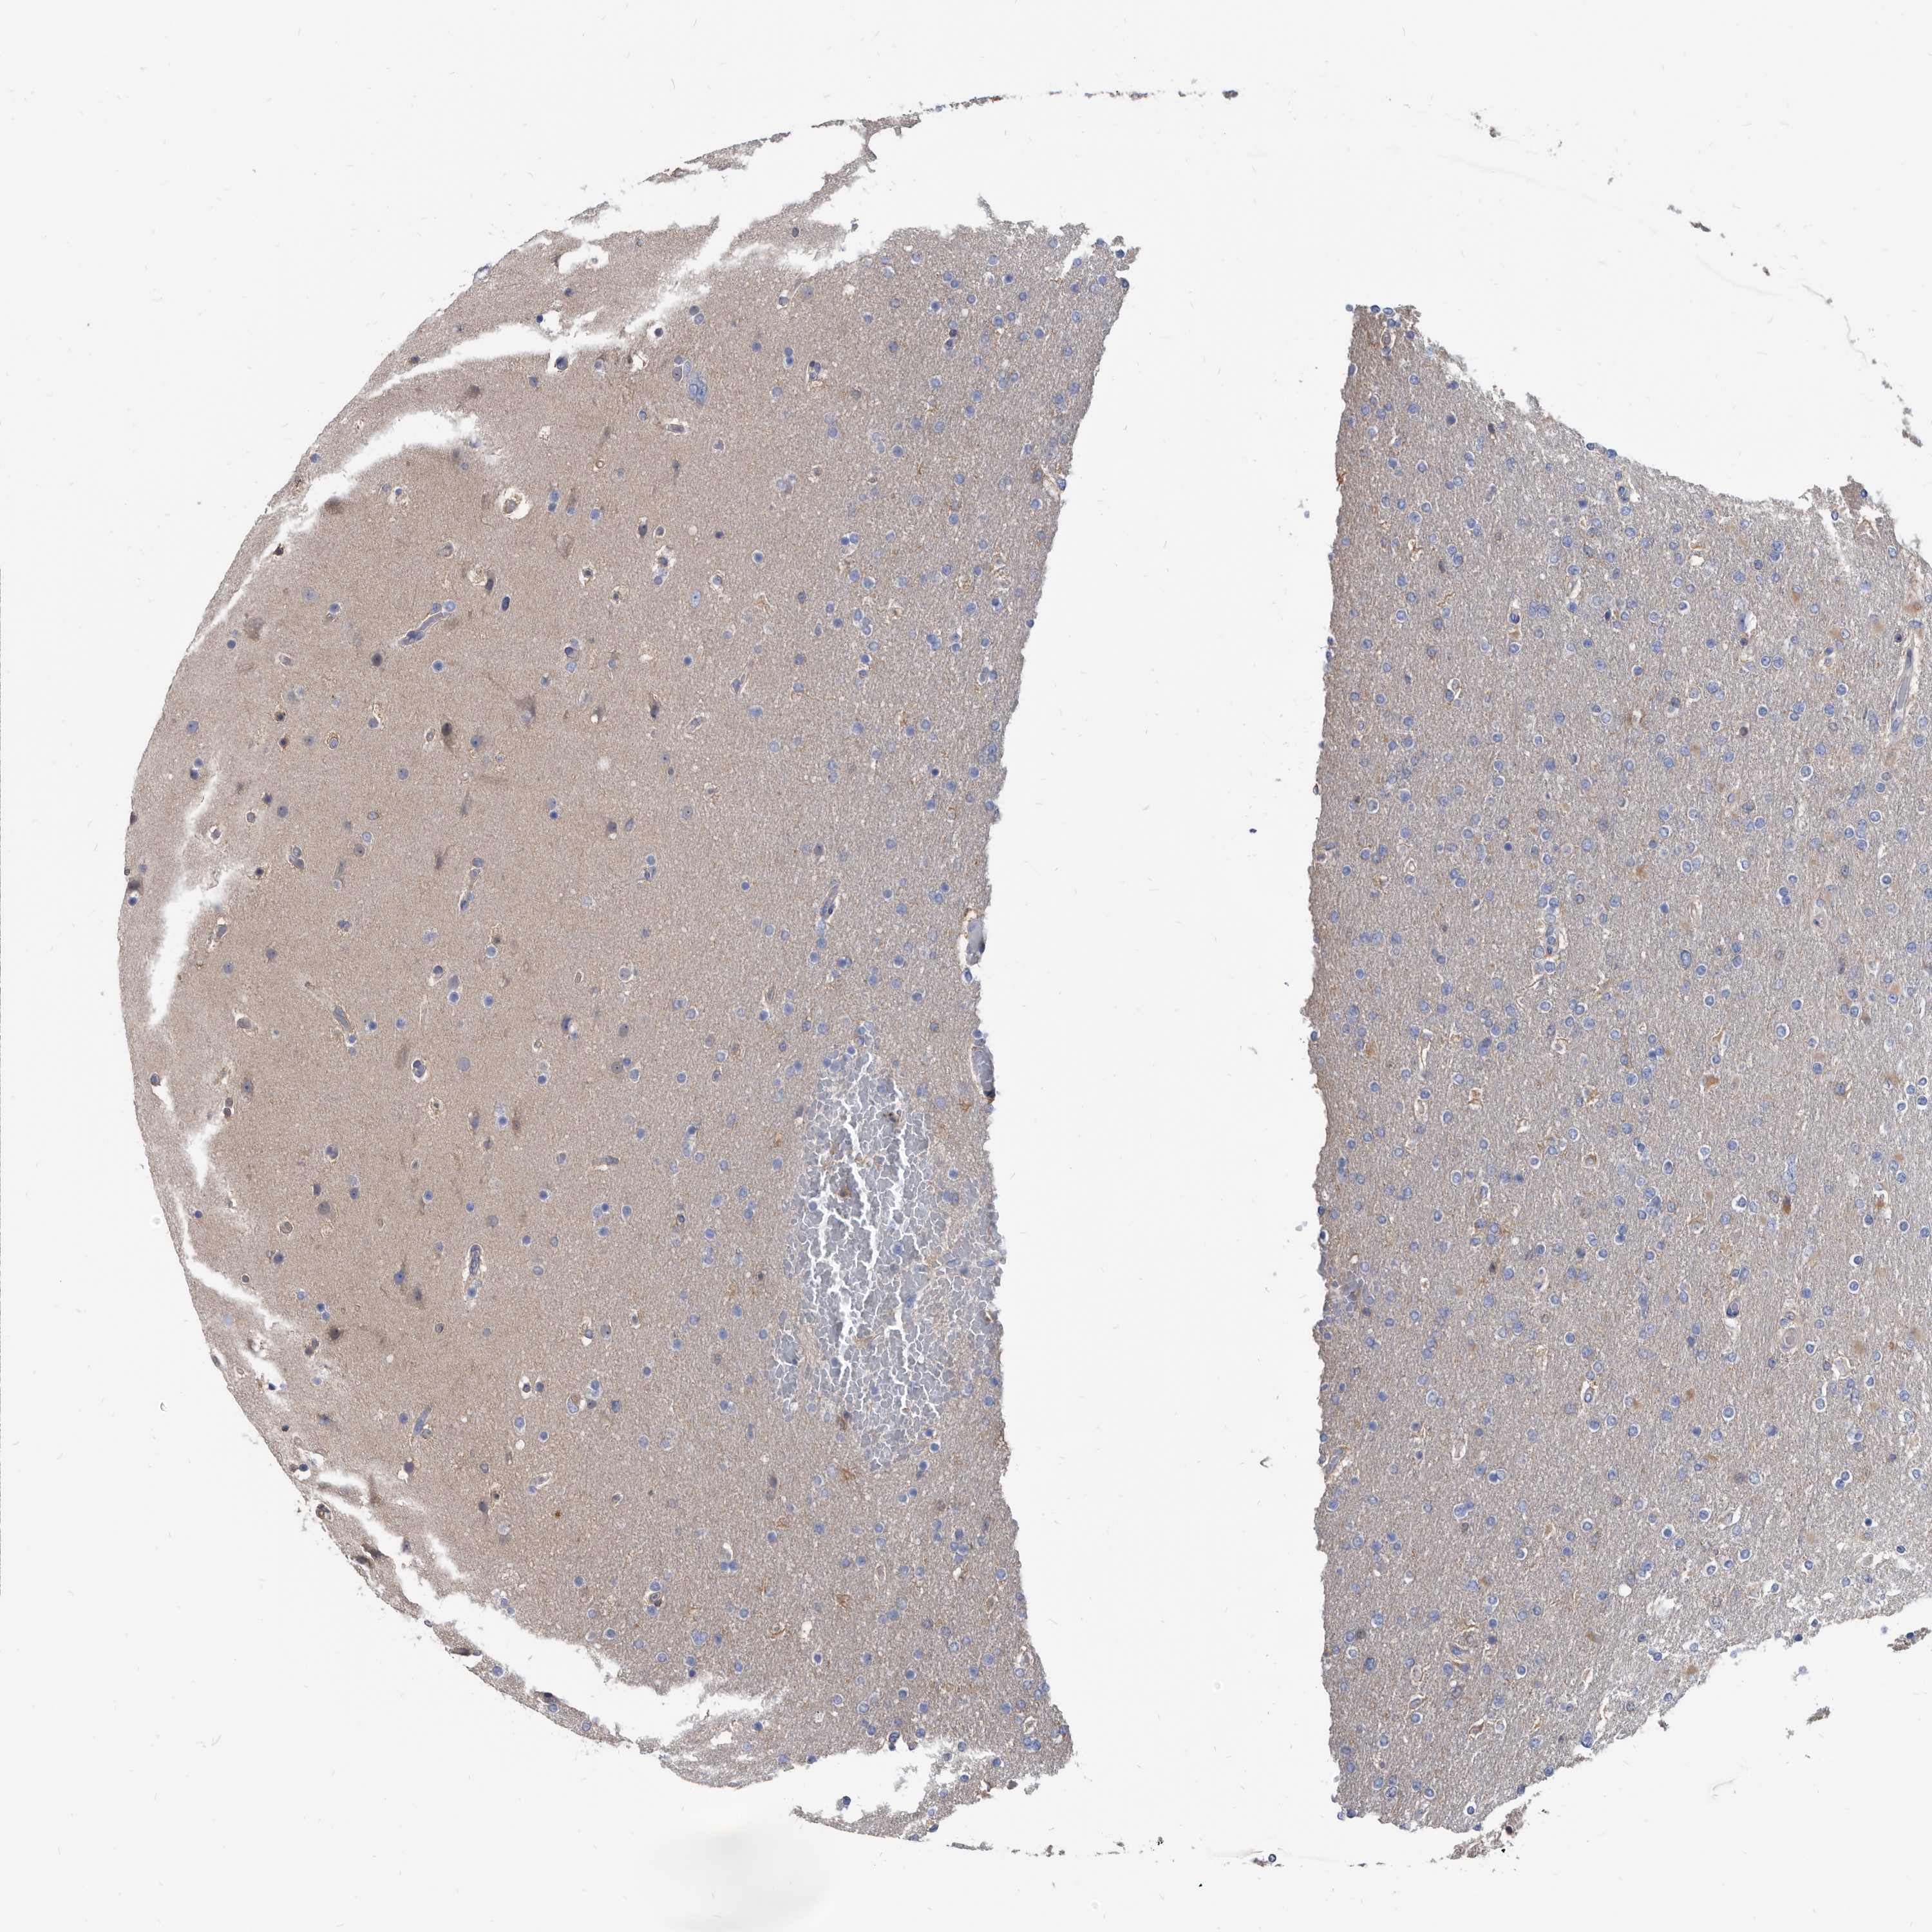

GLIOMA - Protein expressioni

A mouse-over function shows sample information and annotation data. Click on an image to view it in a full screen mode. Samples can be filtered based on level of antibody staining by selecting one or several of the following categories: high, medium, low and not detected. The assay and annotation is described here.

Note that samples used for immunohistochemistry by the Human Protein Atlas do not correspond to samples in the TCGA dataset.

Antibody stainingi

Antibody staining in the annotated cell types in the current human tissue is reported as not detected, low, medium, or high, based on conventional immunohistochemistry profiling in selected tissues. This score is based on the combination of the staining intensity and fraction of stained cells.

Each image is clickable and will lead to virtual microscopy that enables deeper exploration of all samples and also displays staining intensity scores, fraction scores and subcellular localization as well as patient and tissue information for each sample.

Antibody HPA029700

Antibody HPA029701

Antibody HPA029702

Antibody HPA029703

Staining

High

Medium

Low

Not detected

Intensity

Strong

Moderate

Weak

Negative

Quantity

>75%

75%-25%

<25%

None

Location

Nuclear

Cytoplasmic/membranous

Cytoplasmic/membranous,nuclear

Glioma, malignant, High grade

Glioma, malignant, Low grade

Glioblastoma, NOS